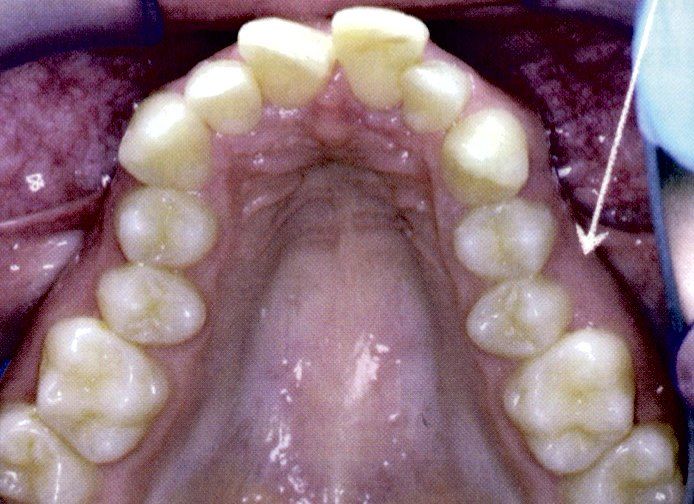

Curare i denti decidui cariati è indispensabile per mantenere

tutto lo spazio possibile per la permuta dei denti permanenti

che spesso sono più grossi che quelli da latte.

Curare bene i denti da latte vuol dire anche evitare, a volte, di far portare l'apparecchio ortodontico al bambino perché mantenendo lo spazio il dente permanente può erompere nel posto corretto.

Diminuiscono gli affolamenti dentali